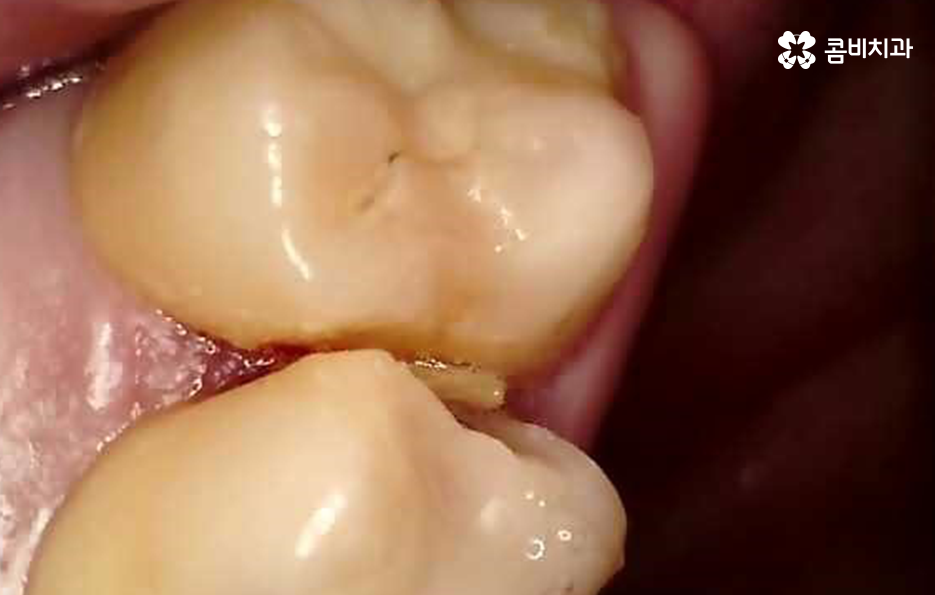

어금니는 사랑니와도 가깝고 나이가 들수록 충치 뿐 아니라 치아의 마모와 균열로 인해 다양한 이유로 손상될 수 있기 때문에 어금니 충치치료 뿐 아니라 파절로 인한 치료를 여러 번 받다보면 결국 인레이 치료를 받거나 신경치료 후 크라운을 씌워야 하는 경우가 많이 있는데요

위 사례에서 보시는 것처럼 어금니 씹는 면에 이미 과거에 보철이나 아말감으로 치료 했던 흔적이 많이 남아 있어요. 어금니는 저작 기능에서 주된 역할을 하기 때문에 치아의 씹는 면에서 충치가 발생하기도 하고 나이가 들수록 치아의 마모로 인한 깨짐이나 균열로 인해 고생하는 분들도 많을 거예요